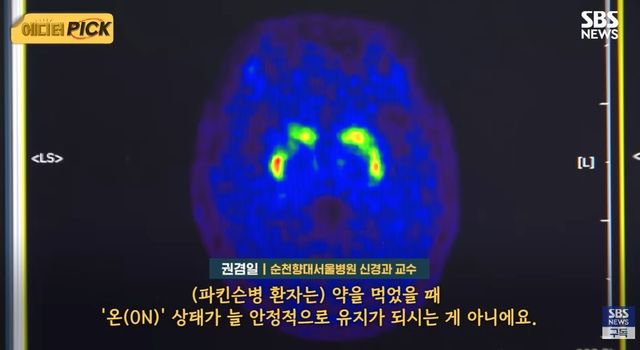

전문가들은 이러한 질환의 특수성이 제대로 반영되지 않고 있다고 지적한다. 권겸일 순천향대서울병원 신경과 교수는 “(파킨슨병 환자는) 약을 먹었을 때 '온(ON)' 상태가 늘 안정적으로 유지가 되시는 게 아니에요. 시력 장애 환자와 동일시해서 장애 평가를 하는 것은, 파킨슨 질환의 특수성을 정말 제대로 반영하지 못하고, 이해하지 못하는 부분이 아닌가….”라고 설명했다.

파킨슨병은 대표적인 퇴행성 신경계 질환으로, 뇌의 흑질에서 도파민을 생성하는 신경세포가 점차 소실되면서 발생한다. 도파민은 신체 움직임을 조절하는 데 중요한 역할을 하는 신경전달물질로, 이 물질이 부족해지면 운동 기능에 이상이 생긴다. 대표적인 증상으로는 손이나 팔이 떨리는 진전, 몸이 뻣뻣해지는 강직, 움직임이 느려지는 서동, 균형 유지가 어려워지는 자세 불안정 등이 있다.